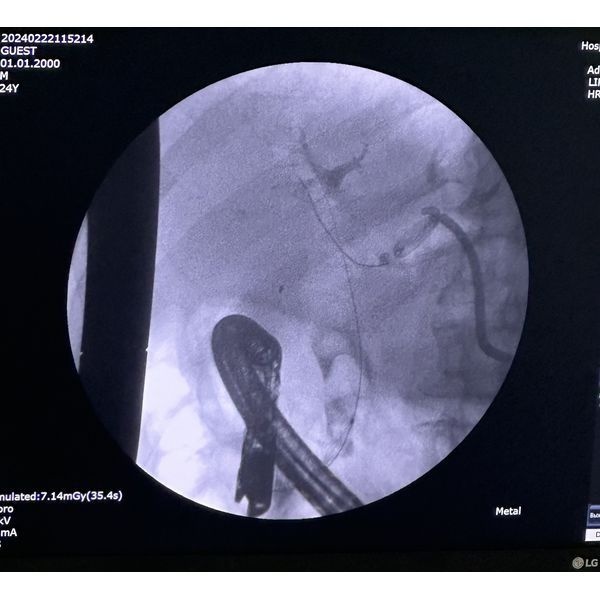

- ретроградную панкреатохолангиографию — комплексное исследование желчных протоков и протоков поджелудочной железы с помощью эндоскопа;

- папиллотомию — расширение выходного отверстия Фатерова сосочка для улучшения оттока желчи из общего желчного протока;

- холедохолитоэкстракцию — извлечение камней.

Однако извлечь крупные камни из общего желчного протока не удалось, поэтому через месяц пациент прошёл ещё одну операцию — наноимпульсное дробление камней (холедохолитотрипсию) с помощью аппарата SpyGlass.